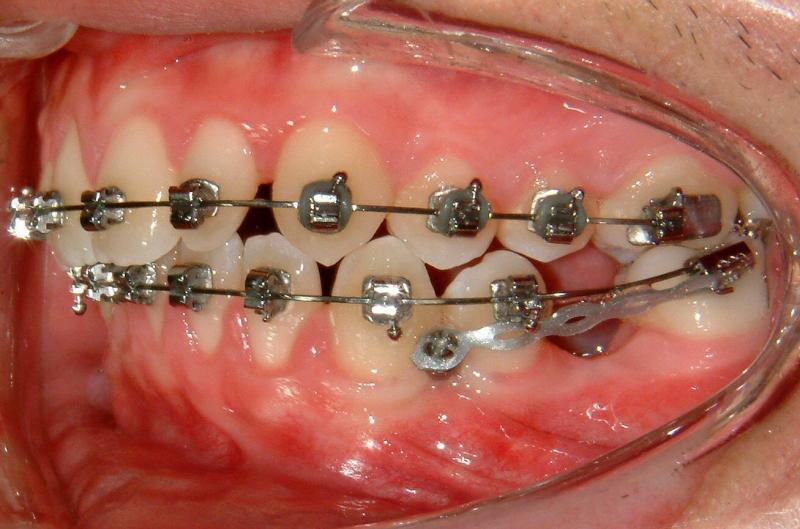

Fig. 6. Immediate loading for TAD (activated)

© Copyright 2007-2014, Vu Orthodontics. All rights reserved.

It can be seen that Figure 6 shows immediate loading with light activation which is necessary for bone modeling.